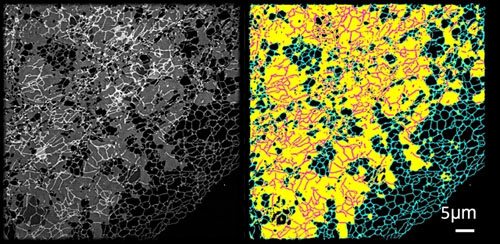

由于內質網是細胞中十分復雜且龐大的動態網絡,其形態和分布非常復雜。據了解,目前科學界沒有很好的方法實現精確定量分析內質網的拓撲結構和運動狀態。劍橋無限極研究中心研究人員通過3年的技術攻關,終于在此領域取得了突破性進展,將人工智能和超高分辨率成像系統結合建立了一套全新的智能分析體系“ERnet”,第一次實現了對活細胞內質網結構的精確定量分析。憑借在技術和科學認識上的顯著創新性,該成果發表在全球科學頂刊、生化研究方法領域排名第一的權威刊物《Nature Methods》(IF47.99)。

本研究則是CIRCE在細胞器和成像研究方面另一重大突破,本次研究重點對象為細胞內質網。“ERnet”基于Transformer的結構搭建而成,是全球現有最先進的機器學習骨干結構,被應用于多款其他人工智能模型中,如ChatGPT即是基于此擴展搭建而成。這個超分辨率成像技術與人工智能的融合給生物學研究帶來了革命性的影響,借助“ERnet”,研究人員發現了一種新的內質網結構——片上管狀內質網,這一發現首次證明了片狀和管狀內質網在結構上有廣泛的交集,更新了科學界對內質網結構、分布和動態的認識,后續能更深入了解其結構與功能紊亂的關系,在科學上具有重要的創新意義。

借助“ERnet”,研究人員還能快速分析不同疾病和健康問題模型中內質網的結構,發現多種類型疾病模型所對應的內質網的結構特征,并給出多參數的量化結果,使得不同條件下的內質網結構能夠在統一的分析框架下進行比較,可應用于健康領域產品的功能因子篩選、功效驗證和機制可視化研究,具有較高的科研和產品轉化應用價值。